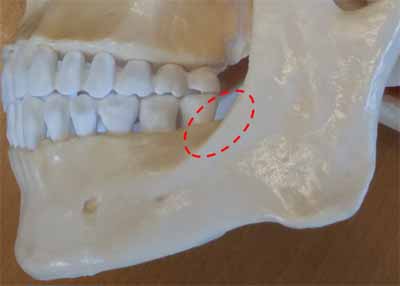

下顎の水平部分から垂直部分(枝)への移行部には、歯列弓の周囲の頬側に強固な骨の縁があります(画像22を参照)。この骨の縁は斜線と呼ばれ、X線では下顎第三大臼歯の歯冠上を走り、第二大臼歯の上を前方に続く透明なエックス線不透過性の線として確認できます(画像23を参照)。

下顎の臼歯部の舌側には、別の骨の隆起である顎舌骨筋線があります。これは口底筋の付着部も形成し、大部分が大臼歯の根の上にエックス線不透過性の水平線として現れます(画像24を参照)。顎舌骨筋線の太さは個人によって異なるため、X線画像では明瞭に見えたり見えなかったりする場合があります。顎舌骨筋線のすぐ下には、境界が不明瞭なエックス線透過性の領域があります。これは下顎の舌側表面にあるくぼみ、顎下窩です(画像24参照)。